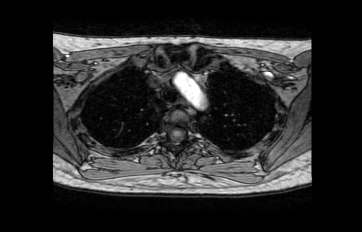

안녕하세요. 이욱현 의사입니다. 사진은 가슴 부근인 것으로 보입니다. 대동맥궁(arch)인 것 같습니다. 대동맥궁에서 뇌로 가는 혈관들이 시작하기 때문에 찍힌 것으로 보입니다.

현재 캡처해 주신 부분은 흉부입니다.

양쪽의 폐 및 가운데 공같은 것은 대동맥에 해당하겠습니다.

질문에 첨부되어 있는 사진은 가슴 부위에 해당되며,

궁금해 하시는 구조물은 정상적인 구조물인 대동맥궁에

조영제가 지나가며 하얗게 강조된 것으로 추측됩니다.정확한 소견은 담당 의료진과 상의하시길 권장드립니다.

중앙에 하얗게 보이는 부분은 대동맥입니다. 뇌를 찍은 장면은 아니고 흉부 영상입니다.

안녕하세요. 채홍석 의사입니다. 상행대동맥의 일부가 보이는 것 같습니다. 첨부해주신 영상은 아직까지 뇌가 보이는 레벨은 아닌 것 같네요

올려주신 사진은 흉부부위의 사진입니다. 말씀하신 가운데 하얀 공같은 것은 혈관입니다. 대동맥궁으로 보이네요.